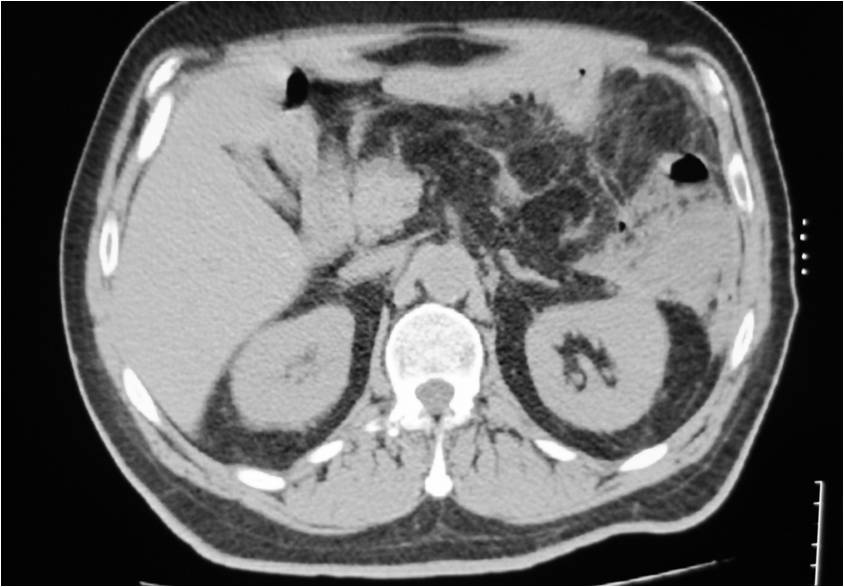

- Large abdominal abscess post- pancreatic surgery

- Successful drainage

- Right sub diaphragmatic abscess post right hemicolectomy